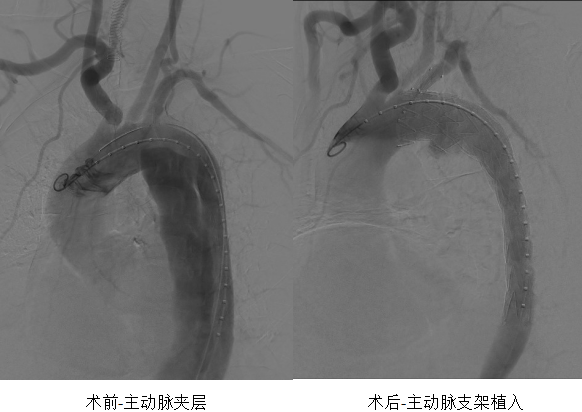

CT室接到電話通知后迅速響應(yīng),準(zhǔn)備工作一氣呵成,從患者進(jìn)入CT室到完成檢查,全程不到10分鐘。CT室醫(yī)生張佳甚緊盯屏幕,第一時(shí)間作出精準(zhǔn)診斷:“Standford B型主動(dòng)脈夾層”。

介入血管科主任余景志在接到電話后,頂著風(fēng)雨第一時(shí)間趕到醫(yī)院。在仔細(xì)查閱患者的影像資料后,他果斷拍板:“具備急診手術(shù)指征,立刻激活介入團(tuán)隊(duì)!”同時(shí),他向麻醉科發(fā)出緊急支援請(qǐng)求:“需要一位有經(jīng)驗(yàn)的麻醉醫(yī)師,術(shù)中必須平穩(wěn)控制血壓!”

一切準(zhǔn)備就緒,患者被平穩(wěn)送入介入手術(shù)室。此刻,介入血管科主任余景志、醫(yī)生沈盼、李江,護(hù)士長(zhǎng)龔明霞、護(hù)士文怡,以及麻醉醫(yī)師劉露早已嚴(yán)陣以待。手術(shù)臺(tái)上,大家配合默契,操作精準(zhǔn);麻醉醫(yī)師劉露緊盯監(jiān)護(hù)儀,將患者血壓維持在理想狀態(tài)。從麻醉開(kāi)始到手術(shù)結(jié)束,整個(gè)過(guò)程僅用時(shí)1小時(shí)30分鐘,這顆隨時(shí)可能“引爆”的“血管炸彈”被成功拆除。